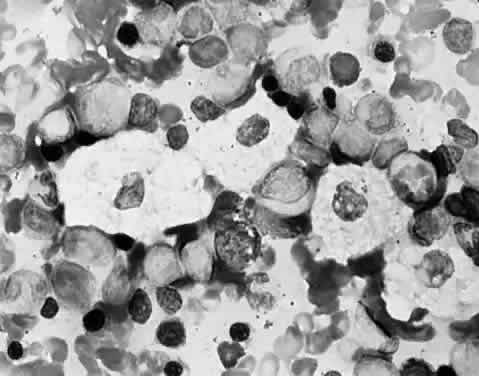

The pathologic hallmark of types A and B is the Niemann-Pick cell, which is a lipid-laden foam cell133 (Fig. 14). Sphingomyelin accumulates in the brain and autonomic ganglia. The neurons become swollen and have a pale cytoplasm. Ultrastructurally, the cells contain concentric lamellated bodies representing storage cytosomes. Inclusion profiles in the viscera, lymph nodes, and foam cells also correlate with an increase in sphingomyelin content. Diagnosis can be made readily by enzymatic determination of ASM activity in cells and tissues. More than 300 cases of type A and B NPD have been reported. Prenatal diagnosis has been accomplished by enzyme assays of cultured amniotic fluid cells in types A and B.

Fig. 14. Foam cells in bone marrow aspirate of patient with Niemann-Pick type B. Giemsa stain.